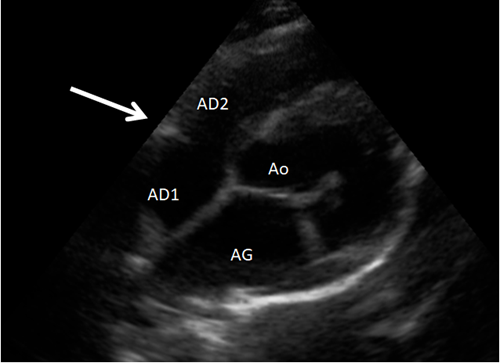

On a une sensation de bombement a certains endroits de l’AD

Doppler couleur

Flux turbulent qui confirme qu’il existe bien ici une membrane avec une turbulence.

Diminution de diamètre peu importante car vitesse peu importante